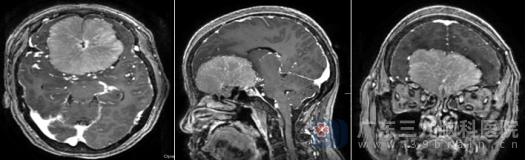

家人带着王阿姨到深圳一家医院进行检查,当核磁共振结果出来时,医生和家人都倒吸一口冷气——王阿姨的前颅窝底部竟长着一个巨大的占位性病变,尺寸约71.3×68.6×42.1毫米,比一个鸡蛋还要大!这个庞然大物压迫着周围的脑组织,导致双侧侧脑室及第三脑室前份受压。

“考虑脑膜瘤可能性大。”医生的诊断让一家人心情沉重。为了寻求更专业的治疗,他们迅速转往广东三九脑科医院神经外十科。

入院检查时,王阿姨左眼视力仅4.3,右眼4.8,已经完全丧失嗅觉。这些症状都与肿瘤的位置和大小密切相关——前颅窝底部的这个巨大肿瘤,早已占满双侧嗅沟,正好压迫着双侧负责嗅觉的嗅神经神经通路。